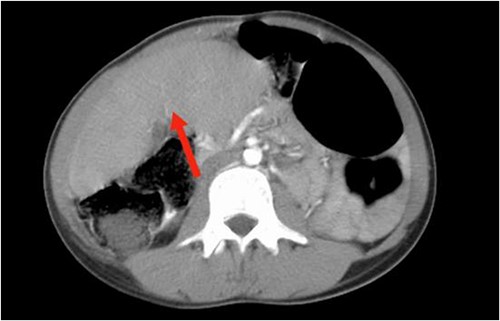

Abdominal ultrasound revealed the spleen was seen in the right lumbar region, displaying mild splenomegaly. The spleen exhibited normal texture and good vascularity. A CT scan, revealed the absence of the spleen in the left upper quadrant and confirmed the diagnosis of a WS (Figs 1 and 2). We also identified elements of splenic pedicle torsion (Fig. 1B), an associated sigmoid volvulus, and dilated tortuous short gastric vessels, indicative of left-side portal hypertension.

The axial plane of the abdominal CT reveals the spleen in the right upper quadrant.